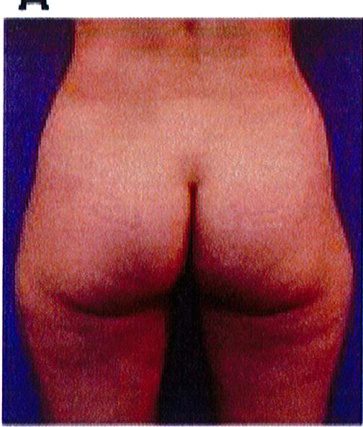

KẾT QUẢ

Cuối cùng, một bệnh nhân 48 tuổi có vùng thắt lưng tương đối phẳng. Với tiền sử đã từng hút mỡ và hiện tại đang mong muốn được làm đầy mông để cải thiện hình thể phần thắt lưng (một cách tương đối). Hai khối implant mi- crotextured thể tích 300 mL được đặt ở dưới cân. Bệnh nhân được tiếp tục điều trị bằng liệu pháp siêu âm (dùng sóng siêu âm) sau phẫu thuật nhằm giảm phản ứng viêm tại chỗ. Sau phẫu thuật không ghi nhận biến chứng (Hình 21).

Hình. 21. (A) Hình anh trước và (B) và sau phẫu thuật làm đầy mông của bệnh nhân có vùng thắt lưng tương đối phẳng. Bệnh nhân được đặt khối im- plant dưới cân thế tích 330 mL ở hai bên.